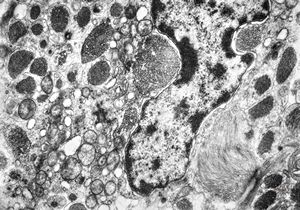

F,50y. | progressive multifocal leukoencephalopathy- viral particles in a glial cell

F,50y. | progressive multifocal leukoencephalopathy- viral particles in a glial cell

F,50y. | progressive multifocal leukoencephalopathy- viral particles in a glial cell